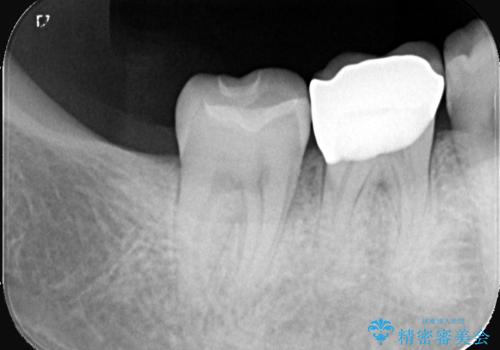

- 主訴:銀色の詰め物が取れてしまった。下の歯は笑うと見えるので、これを機に白くしたい。

保険適用のメタルインレーが脱離しており、歯冠色で審美性、適合性の良いセラミックインレーでのやり替えを提案しました。

メタルインレーが脱離した咬合面の窩洞内は、う蝕を除去し、セラミックインレーの厚みの担保とメタルタトゥー部分の除去を目的に形成を行いました。

インレーセット時はラバーダム防湿を行っています。